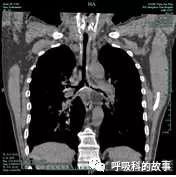

图8气道三维重建见气道壁弥漫增厚及管腔局部狭窄;

图9纵隔窗示气道壁弥漫增厚。